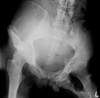

42

What is the most likely diagnosis? What bones are involved?

AVN of femoral head

47

What is demonstrated in the right ilium?

Hemophiliac pseudotumor (geo. Lytic lesion)

48

What is occurring medial to the left hip?

Myositis ossificans